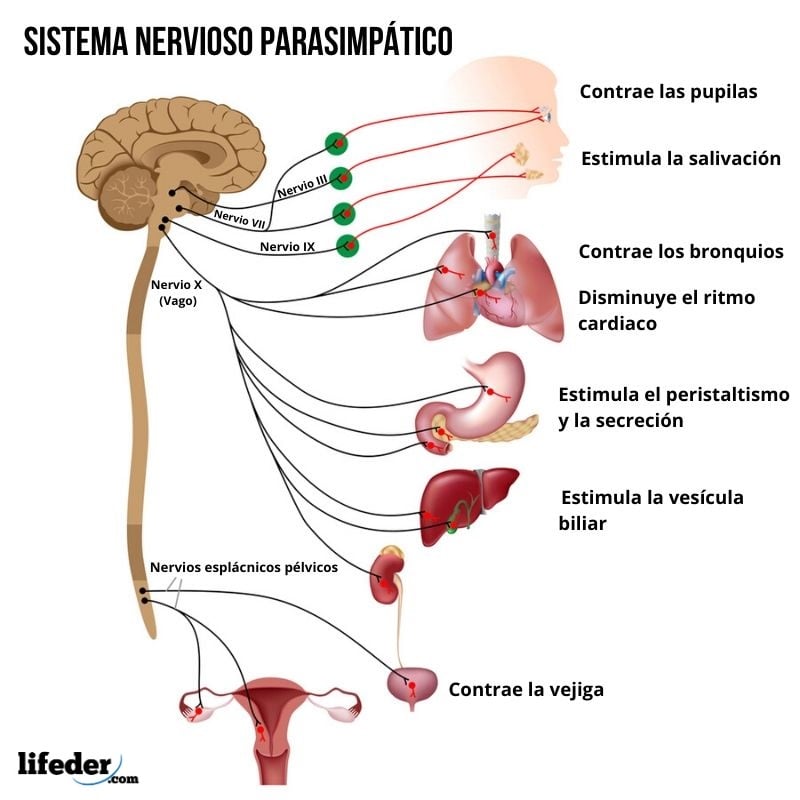

Neuroanatomía

Es una especialización de las neurociencias que se encarga de estudiar el funcionamiento del sistema nervioso y de los órganos de los sentidos en sus aspectos clínicos, descriptivos y topográficos.